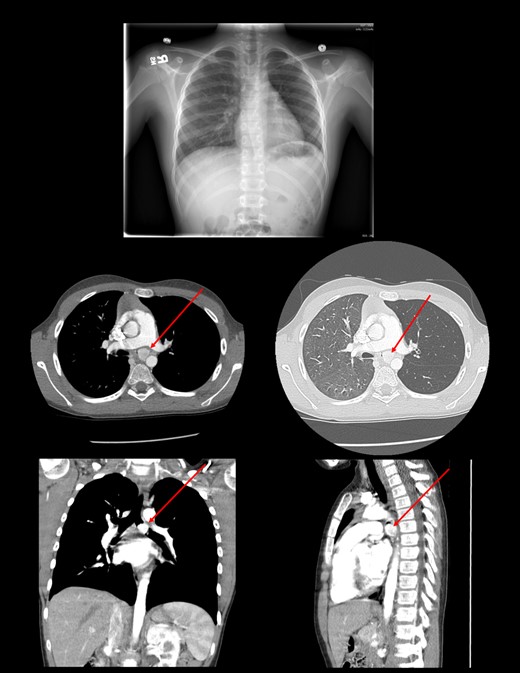

The patient is a 10-year-old boy who presented to an emergency room with hemoptysis. Work-up showed normal laboratory findings and negative Quantiferon gold. Radiography of the chest showed hyperinflation on the left lung. Subsequent CT scan of the chest showed a 1.7 cm hypervascular mass in the proximal left main-stem bronchus.

Chest radiography showed dilation of the proximal left main-stem bronchus with focal truncation distally. Review of his chest CT confirmed a large hypervascular mass in the left main-stem bronchus (Fig. 1).